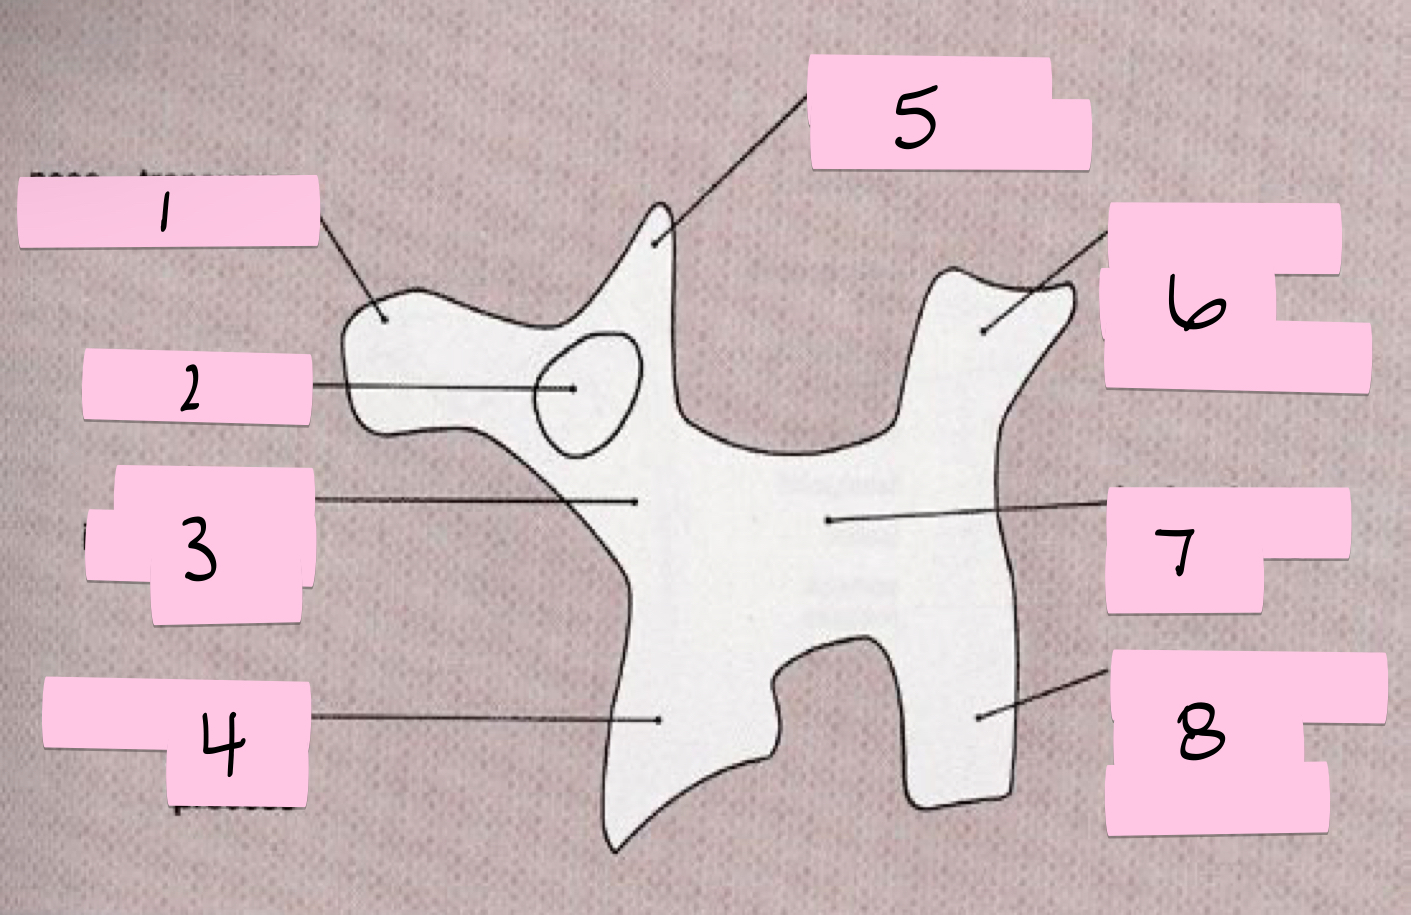

What is 1 pointing to?

Nose- Transverse process

What is 2 pointing to?

Eye- Pedicle

What is 3 pointing to?

Neck- Pars interacticularis (isthmus)

What is 4 pointing to?

Foreleg- Inferior articular process

What is 5 pointing to?

Ear- Superior articular process

What is 6 pointing to?

Tail- Superior articular process of opposite side

What is 7 pointing to?

Body- Lamina and spinous process

What is 8 pointing to?

Hindleg- Inferior articular process of opposite side